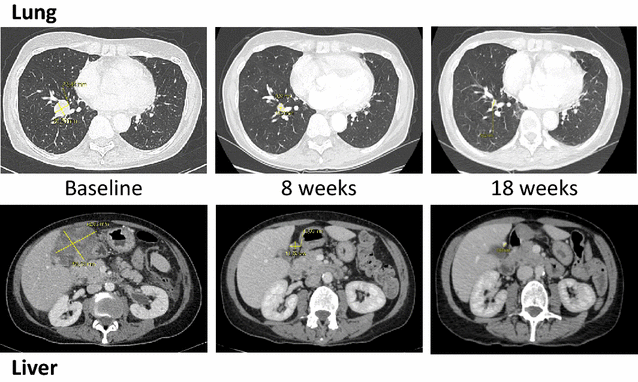

Tumor assessment according to Response Evaluation Criteria in Solid Tumors, version 1.1 [12], performed with a computed tomography scanner, showed a dramatic response after 8 weeks (86% reduction of the tumor burden). With a 20-week follow-up period, treatment was still ongoing and the response maintained [almost complete response observed at week 18: all target and non-target lesions became non-measurable and no new lesions were observed (Fig. 1)].